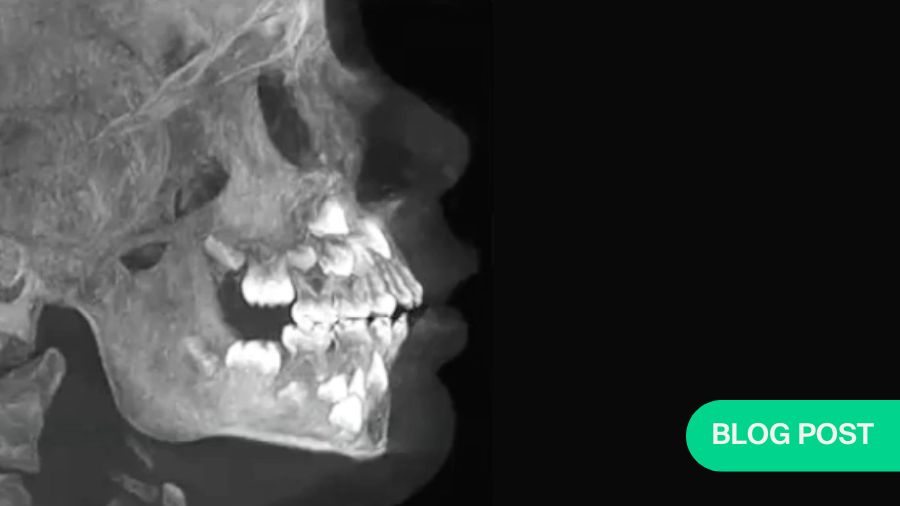

We saw that the growth outcomes and jaw functions were better in patients who have undergone a costochondral graft than the patients who have not undergone a costochondral graft. We found that the costochondral reconstructive osteoplasty in pediatric patients has a better outcome, in terms of growth of the mandible, improvement of the lower facial height, chin deviation, and facial asymmetry and occlusal tilt. The finding supports our hypothesis that the superiority of costochondral graft in pediatric TMJ reconstructions.

Furthermore, we examined whether costochondral grafts fulfill the ramus-condyle unit reconstruction goals in children with temporomandibular joint ankylosis, and we found that yes, it plays a significant role in the treatment of TMJ ankylosis in children, or TMJ reconstructions in children.

We found that 55% of our patients had optimal growth, 41% had suboptimal growth and 4% had overgrowth. The important fact is that 96% were showing some kind of growth. That is good enough for me because these patients, once they are mature, can be managed through other maxillary surgery.

But compared to the costochondral graft, which we published in 2021, the overjet is actually decreasing. The mandible is definitely growing. What will happen when these children mature? I speculate that either I will have to replace or do a revision surgery for the ramus component, or I have to do a revision surgery for fossa and ramus component both, or I may have to do a conventional orthognathic surgery for the asymmetry and maxillary cant, which may not get corrected in these patients.

My take home message is that growth considerations make costochondral graft the logical choice for reconstruction of TMJ in children.